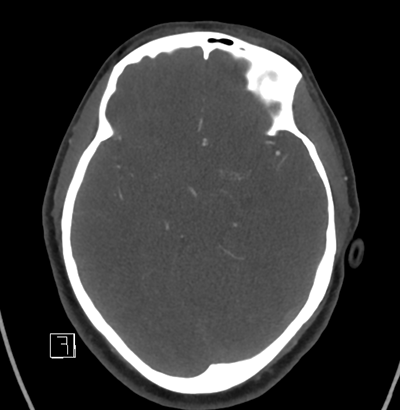

NCHCT

With that in mind, as we look at her neuroimaging, it's subtle, but we can appreciate a faint SAH in the left frontal lobe convexity. Her vessel imaging is unremarkable.